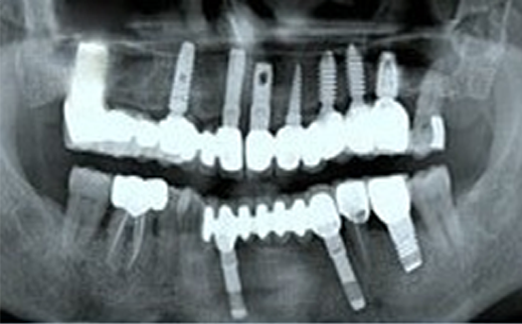

Implants vs. Dental Bridges

• Natural Replacement: Implants provide a more natural and cost-effective solution compared to bridges, which involve altering healthy teeth.

• Longevity: While bridges may last 5-10 years, implants offer a lifetime of functionality and durability.

(13 years After Placement)

“Dental implants prevent bone loss and preserve jaw strength and aesthetics.”

“Dental bridges risk gum disease, jaw shrinkage, and aging effects like wrinkles and bridge loss.”